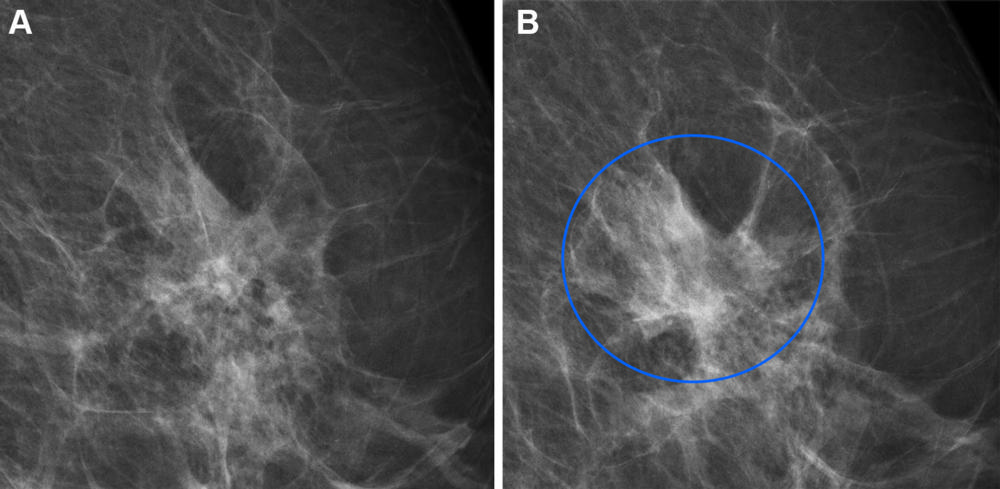

Figure 5. Full-field digital mammograms (left mediolateral oblique view) in a 60-year-old woman with an interval cancer show (A) the screening mammogram at the area of interest and (B) the same area of interest on a clinical mammogram obtained during diagnostic testing a year later, whereby the blue circle indicates the diagnosed lesion. The woman was not recalled as a result of screening. The screening mammogram (A) had a very high combined risk score (highest 99%) as determined by the combination model with texture risk and the examination score.

High-res (TIF) version

Figure 6. Full-field digital mammograms (right mediolateral oblique view) in a 59-year-old woman with a long-term cancer show (A) the screening mammogram at the area of interest and (B) the same area of interest on a clinical mammogram obtained during diagnostic testing 3 years later, whereby the blue circle indicates the diagnosed lesion. The woman was not recalled as a result of screening. The screening mammogram (A) had a very high combined risk score (highest 99.9%) as determined by the combination model with texture risk and the examination score. The four objects are surgical clips left in the breast from previous breast-conserving surgery.